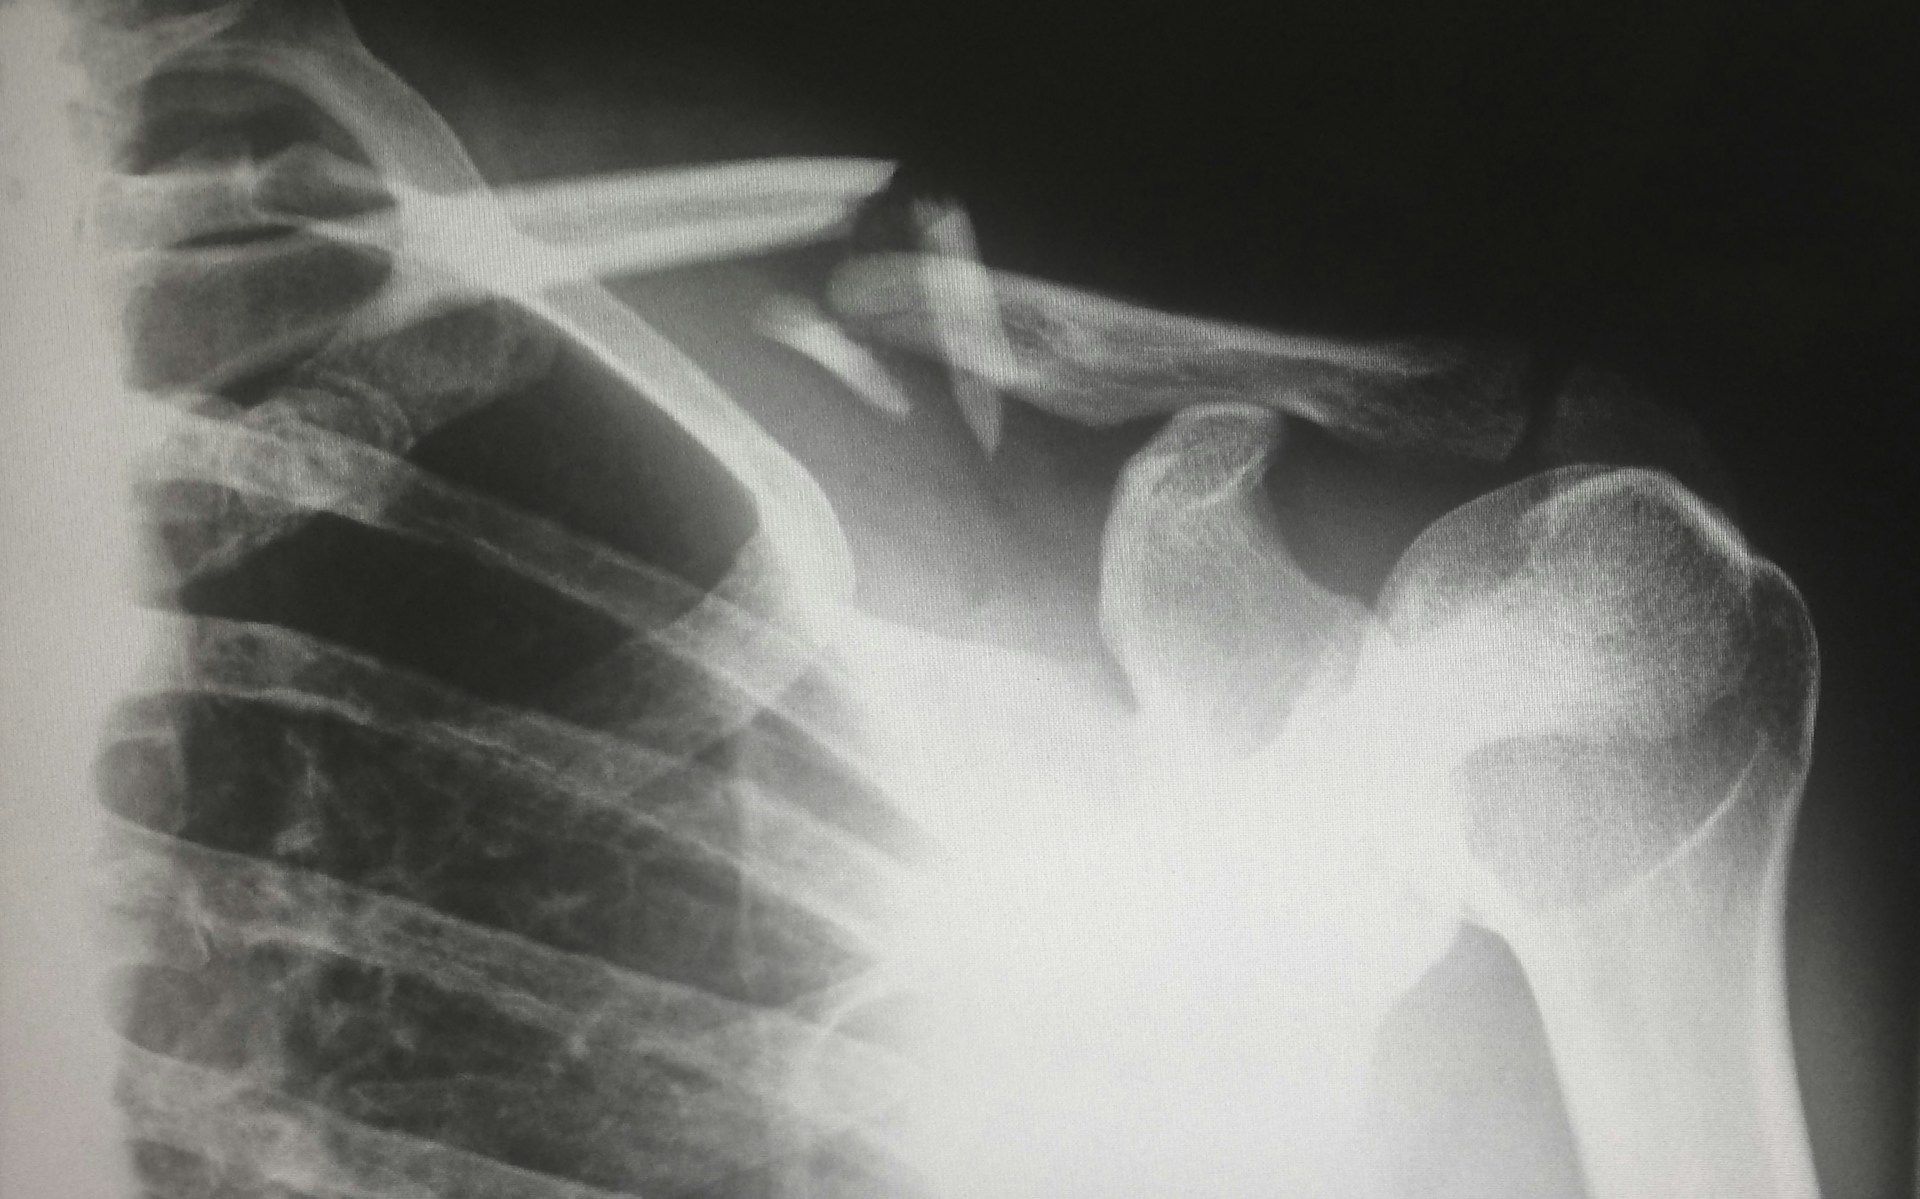

Визначити тип перелому не складно. Якщо шкіра розірвана, а пошкоджену кістку видно перелом називається відкритим. Якщо ж шкіра залишається неушкодженою, перелом вважається закритим.

Класифікувати переломи можна за різними критеріями: за напрямком лінії розлому (подовжні, поперечні), за місцем пошкодження (в області тіла кістки, головки) і за ступенем тяжкості (зі зміщенням або без нього).